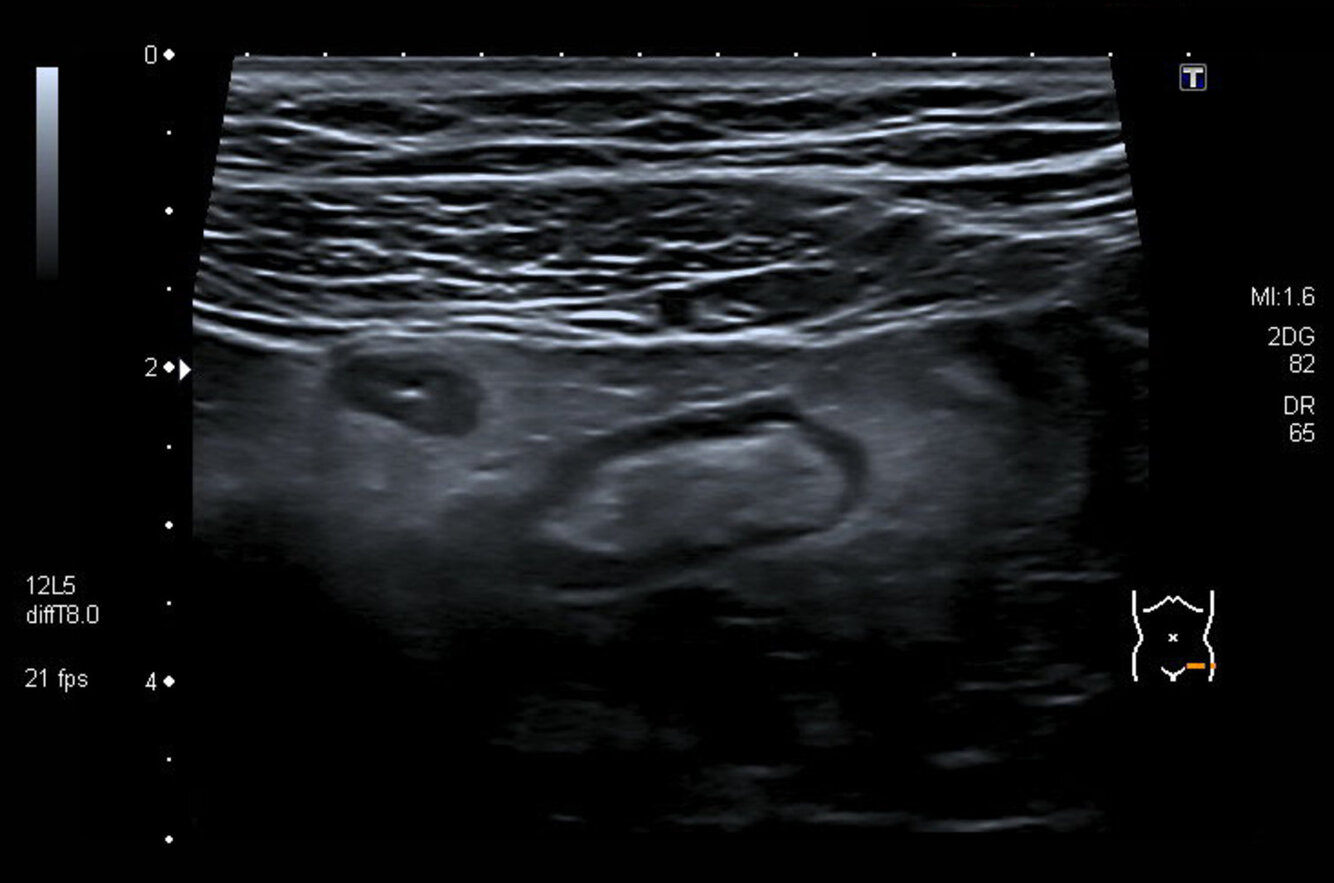

Sigmadivertikulitis (Sonographie)

Sigmadivertikulitis

Sonografischer Querschnitt des linken Unterbauchs:

Bei dem ovalen echoarmen Areal (grün markiert) im Bild links handelt es sich um ein quer angeschnittenes Kolondivertikel, in dessen Zentrum ein kleiner, echoreicher Luftreflex (Pfeil) zu sehen ist. Um das Divertikel herum zeigt sich eine echoreiche Umgebungsreaktion von Omentum majus und Serosa, die als „Netzkappe“ bezeichnet wird. Der Befund spricht für eine Divertikulitis.

Im Bild rechts ist ein Teil des Colon sigmoideum (S) angeschnitten, dessen Wand verdickt ist. Die Wandschichtung ist lediglich verwaschen erkennbar.